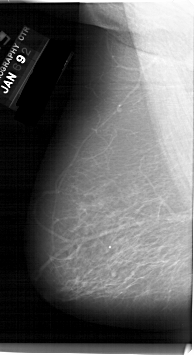

A_1129_1.RIGHT_MLO

RIGHT_MLO LINES 5881 PIXELS_PER_LINE 3106 BITS_PER_PIXEL 12 RESOLUTION 43.5 OVERLAY

FILE: A_1129_1.RIGHT_MLO.OVERLAY

TOTAL_ABNORMALITIES 1

ABNORMALITY 1

LESION_TYPE CALCIFICATION TYPE PLEOMORPHIC DISTRIBUTION SEGMENTAL

ASSESSMENT 4

SUBTLETY 2

PATHOLOGY MALIGNANT